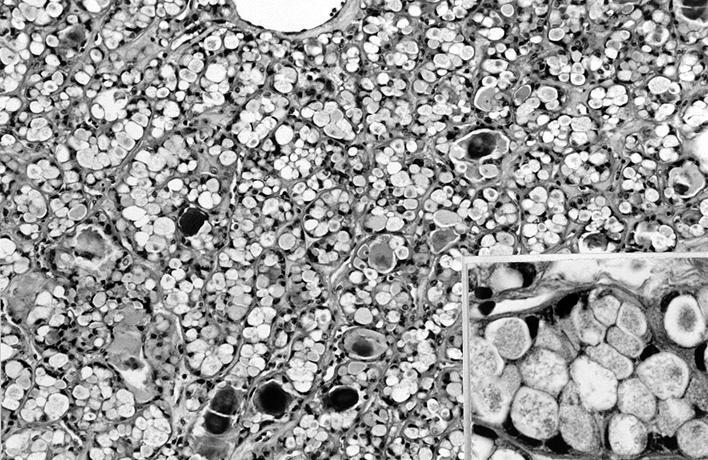

Microscopic (histologic) images

Contributed by Shipra Agarwal, M.D., Andrey Bychkov, M.D., Ph.D., Mark R. Wick, M.D., Asmaa Gaber Abdou, M.D. and AFIP

Patterns:

- Microfollicular (fetal): smaller follicles, small amount of intraluminal colloid

- Macrofollicular (colloid): large follicles, flattened epithelium, abundant colloid

- Hyperfunctioning adenoma (Plummer adenoma): tall columnar epithelium, papillary infoldings, vacuolated cytoplasm, watery colloid showing scalloping

- Follicular adenoma with papillary hyperplasia: cystically dilated follicles, intraluminal papillae

- Lipoadenoma: adipocytic metaplasia of the follicular adenoma

- Follicular adenoma with bizarre nuclei: may be seen after radiation exposure and in hyperfunctioning adenoma

- Signet ring cell follicular adenoma: signet ring cell change

- Clear cell follicular adenoma: follicular adenoma with clear cell change

- Spindle cell follicular adenoma: spindle cell metaplasia

- Black follicular adenoma (black pigment in tumor cell cytoplasm; in patients on minocycline therapy)